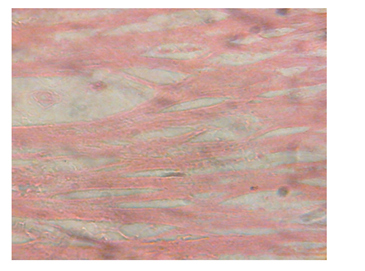

Figure 10 Heart micrograph of control rat showing normal cardiac muscle structures at 3 and 5 weeks.

Figure 11 Heart section of diabetic rat showing no alterations of the cardiac muscle structures at 3 and 5 weeks.

The structural changes in the kidneys could be attributed to altered metabolism in diabetes Rasch,62 and subsequent effects on the increased renal threshold for hyperglycemia.29 Moreover, glucose overload damages the mesangial cells in the renal glomerulus through oxidative stress Brownlee.63 In the diabetic kidney, enhanced glucose uptake occurs in many cell populations including glomerular epithelial cells, mesangial cells and proximal tubular epithelial cells leading to the excessive production of intracellular ROS, making these cells particularly susceptible to diabetic milieu Forbes et al.;64 Eze,65 reported some degeneration of glomeruli with presence of tubular casts and signs of chronic inflammation in diabetic wistar rats. Peter et al.66 had previously reported a damaging effect of diabetes in the glomerulus, thereby affecting Glomerular Filtration Rate (GFR). Zafar et al.67 also reported that streptozotocin-induced diabetic rats showed some functional and morphological changes in the kidney. These morphological abnormalities in the kidney of diabetic rats were associated with significant elevations in serum urea and creatinine levels, indicating impaired renal function of the diabetic animals. The results are consistent with those of Shah et al.68 who reported elevated serum urea and creatinine levels as a result of renal damage in diabetic rats. The histological sections of the hearts of diabetic as well as non-diabetic rats showed normal architecture of the myocardium for the study period. This is consistent with the work done by Kita et al.69 who reported short-term metabolic disorders in diabetic rat heart with histopathological changes occurring later. The results disagree with those of Komolafe et al.24 who reported architectural alterations in myocardium and microanatomy of cardiovascular structures of diabetic animals. In the present study, serum lipid profile was used to assess the risk of development of cardiovascular disease which recorded elevated total cholesterol, LDL-C, VLDL-C and triglyceride levels whereas HDL-C levels decreased in alloxan-induced diabetic rats which is associated with cardiovascular diseases as seen in diabetes. The abnormal high levels of serum lipids in diabetes is mainly due to increased activity of hormone sensitive lipase in insulin deficiency resulting in enhanced lipolysis and mobilization of free fatty acids from the peripheral depots and adipose due to underutilization of glucose. Some of the excess fatty acid produced is then metabolized to acetyl coA which is used in the synthesis of cholesterol in the liver, thus increasing cholesterol levels in diabetes. On the other hand, glucagon, catecholamines and other hormones may also enhance lipolysis. Therefore, the uninhibited action of lipolytic hormones on the fat depots may be responsible for this increase. The lack of insulin and elevations of counter regulatory hormones lead to activation of enzyme (hormone-sensitive lipase) that stimulate lipolysis and enhance release of free fatty acids from adipose tissue. The fatty acids from adipose tissues are mobilized for energy purpose, and excess fatty acids are accumulated in the liver, which are converted to triglycerides Suryawanshi et al.70 The high levels of LDL-C may be attributed to diminished levels of LDL receptors resulting in increased circulating LDL particles Suryawanshi et al.70 The decreased serum HDL-C levels in the present study may enhance CVD risk since HDL-C function is to remove cholesterol atheromas within arteries and transport them back to the liver for excretion and re-utilization. The results support the works of21,23,24,40,68 who reported marked increase in cholesterol, triglycerides, LDL-C, VLDL-C and decreased HDL-C in diabetic rats when compared to non-diabetic rats. However, Jos et al.71 reported no correlation between diabetes mellitus and lipids in the study conducted with diabetes patients.